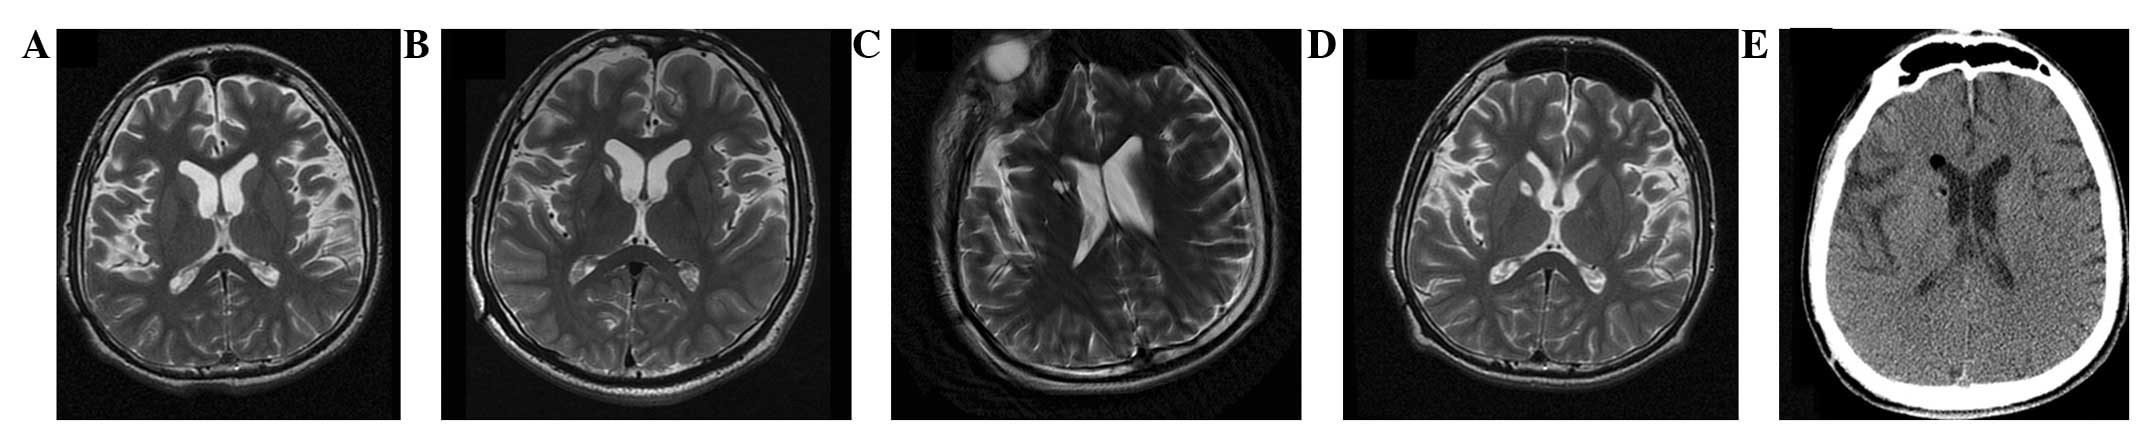

(A) 术前 MRI 显示脑萎缩。 (BD)术后1年、3年、4年MRI与术前MRI相比无明显变化。 (E) 术后3天,计算机断层扫描显示没有出血或水肿。

遗传分析发现患者DYT1 ( TOR1A )第五外显子存在突变 (907-909 delGAG) 。他对神经外科手术表现出良好的耐受性,并于4点出院。没有与细胞植入或外科手术相关的严重不良事件。POD时的CT扫描显示没有出血或水肿(图2e)。术后1个月,患者的PTD症状开始改善。BFMDMS逐渐增加,从术前的21分别增加到术后1、2、3和4年的18、17、15和13,术后4年改善38.1%(表1)。

CT(图1b-e)和MRI(图2b-d)扫描显示4年随访期间没有显着变化。 手术前1天(图1f)和手术后1、2、3和4年(图1g-j) 获得18F-FDGPET扫描。术后双侧植入部位豆状核和丘脑18F-FDG摄取值较术前增加。这一结果表明,自移植以来,葡萄糖代谢逐年略有增加。